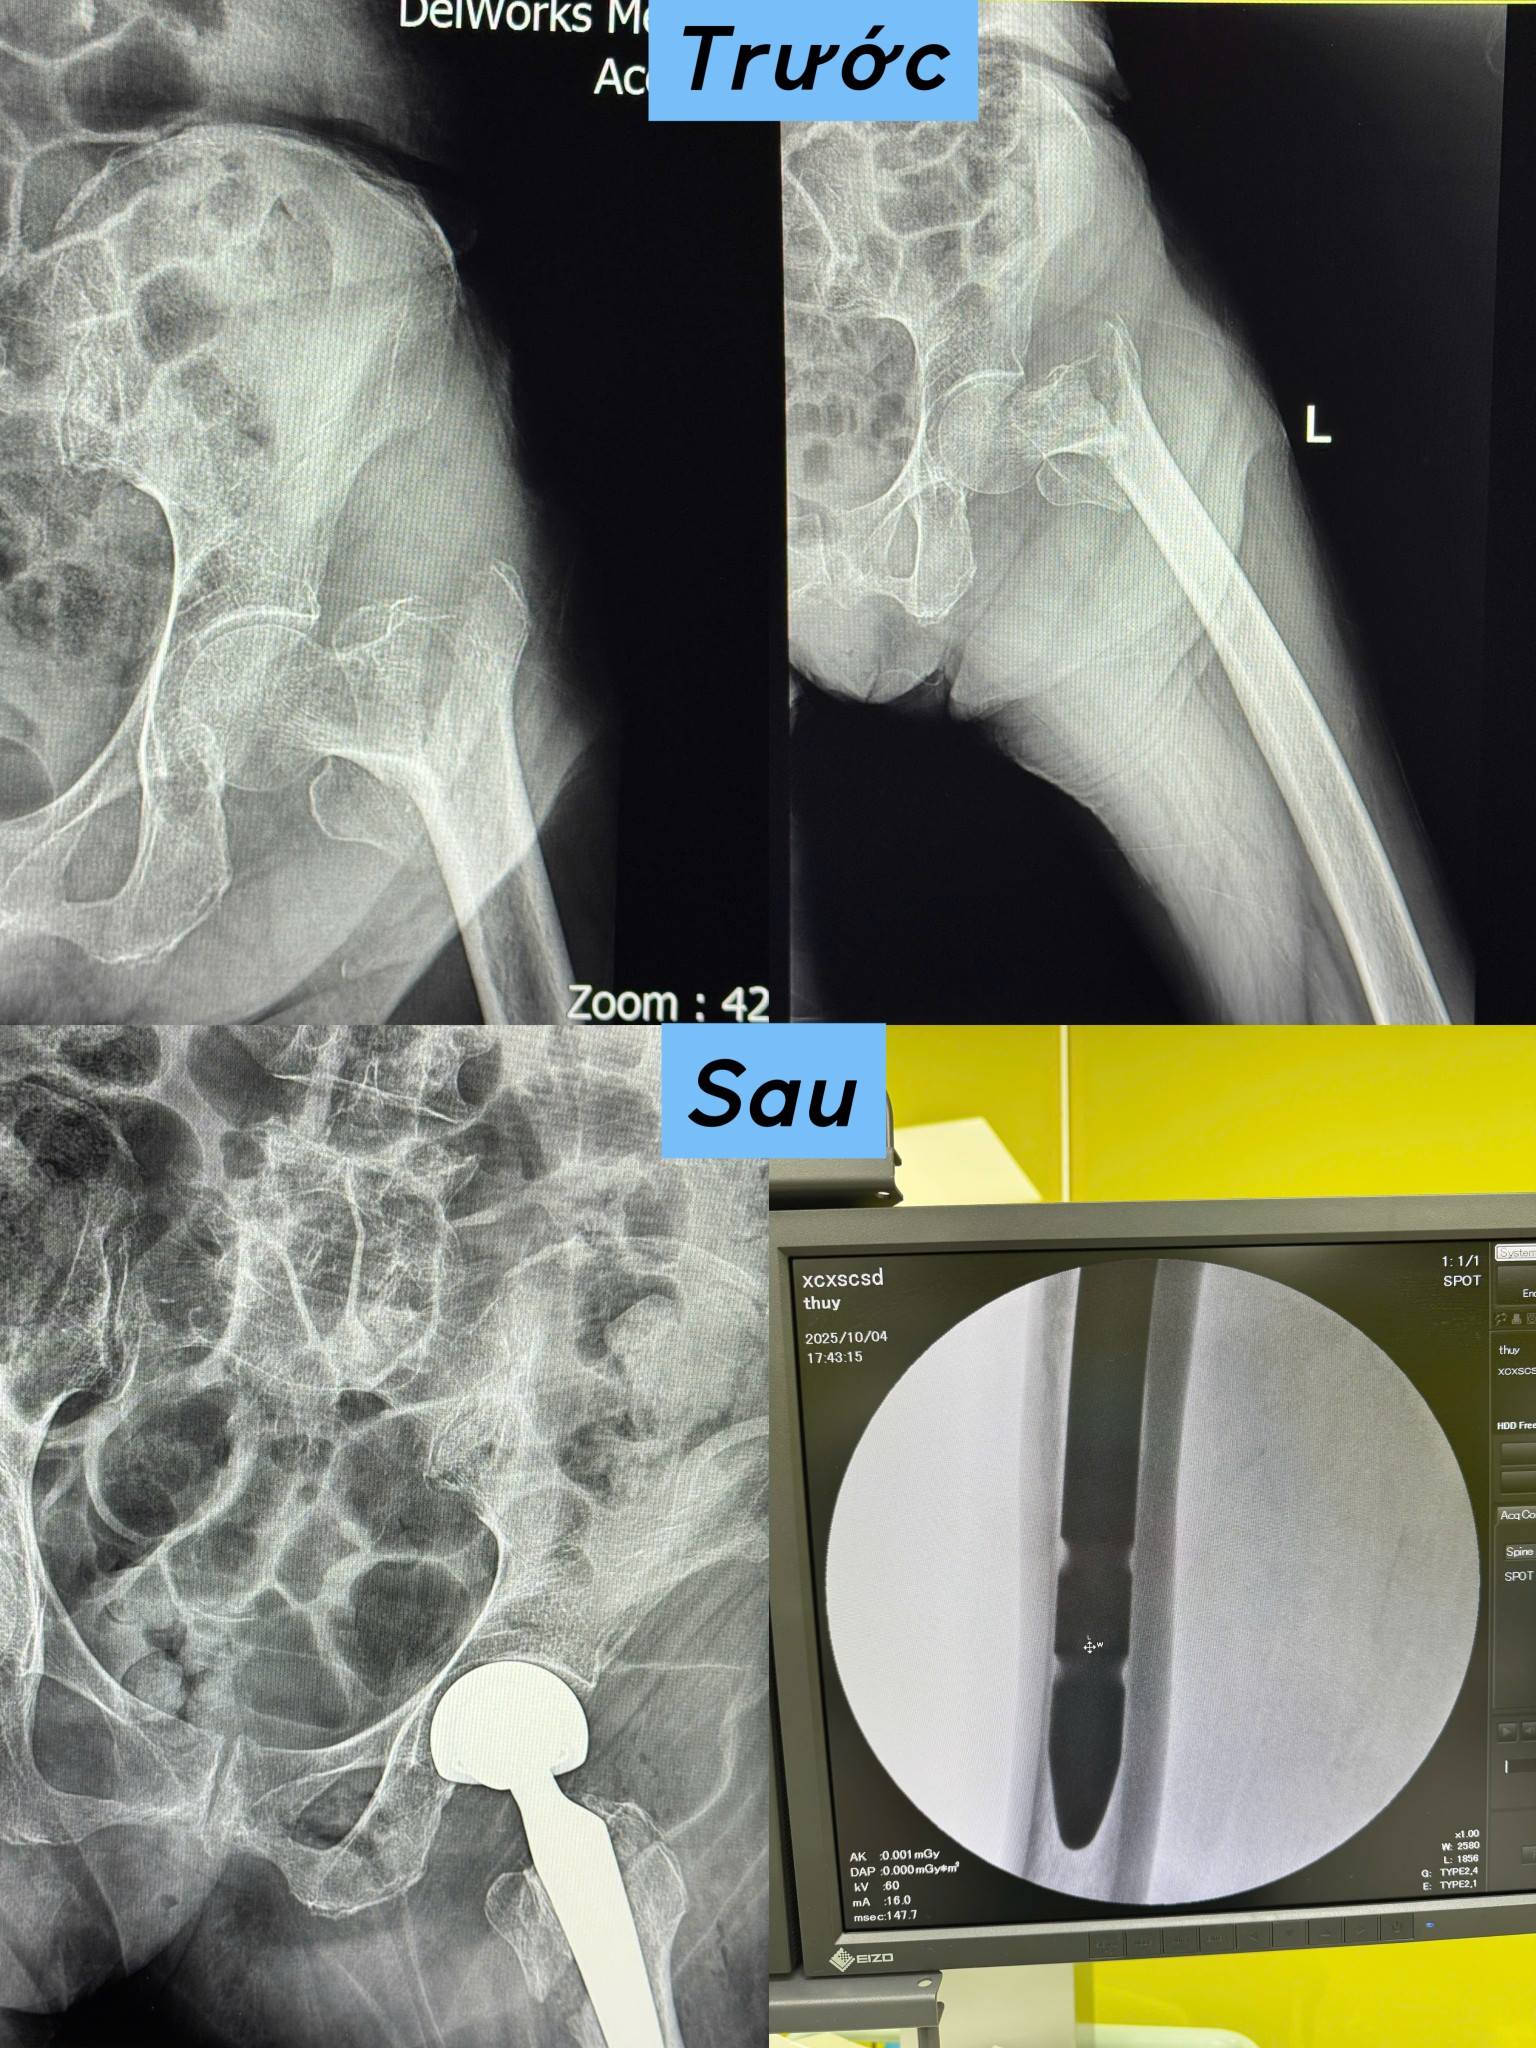

THÀNH CÔNG CA PHẪU THUẬT THAY KHỚP HÁNG BÁN PHẦN CHUÔI DÀI Ở CỤ BÀ 91 TUỔI - BƯỚC TIẾN TRONG LÀM CHỦ KỸ THUẬT CHUYÊN SÂU TẠI BỆNH VIỆN ĐA KHOA KHU VỰC QUẢNG YÊN

Trong hành trình chăm sóc và bảo vệ sức khỏe nhân dân, mỗi ca phẫu thuật thành công đều là một cột mốc ý nghĩa. Mới đây, các bác sĩ khoa Phẫu thuật, khoa Ngoại – Bệnh viện Đa khoa khu vực Quảng Yên đã thực hiện thành công ca phẫu thuật thay khớp háng cho bệnh nhân Đoàn Thị G, 91 tuổi, địa chỉ: khu Bãi 4, phường Quảng Yên, tỉnh Quảng Ninh. Bệnh nhân nhập viện trong tình trạng gãy liên mẫu chuyển xương đùi trái, thiếu máu, nhiều bệnh lý nền phức tạp và sức khỏe yếu.

Ảnh chụp X-quang trước và sau phẫu thuật

Trước tình trạng khó khăn đó, các bác sĩ ngoại khoa, bác sĩ gây mê hồi sức cùng đội ngũ điều dưỡng tận tâm, giàu kinh nghiệm đã nhanh chóng tiến hành hội chẩn liên khoa, đánh giá toàn diện tình hình sức khỏe, truyền máu, kiểm soát bệnh nền và lựa chọn phương án phẫu thuật tối ưu thay khớp háng bán phần chuôi dài. Đây là một kỹ thuật cao, đòi hỏi sự phối hợp chính xác, kinh nghiệm và bản lĩnh vững vàng của toàn bộ bác sỹ, đặc biệt là vai trò then chốt trong việc kiểm soát những nguy cơ trước, trong và sau mổ.